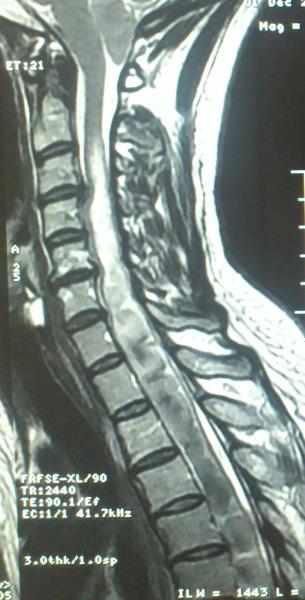

Ασθενής  γυναίκα 49 ετών προσήλθε λόγω υπινιακής κεφαλαλγίας εκλυόμενης και επιδεινούμενης  κατά την επίκυψη και  την άρση βάρους  ( Valsalva maneuvers ) με συνοδό αίσθημα αιμωδιών  άνω και κάτω άκρων. Ο προεγχειρητικός έλεγχος με μαγνητική τομογραφία  του κρανιοσπονδυλικού άξονα ανέδειξε εικόνα συμβατή με Chiari τύπου I : κατάσπαση των παρεγκεφαλιδικών αμυγδαλών 8 mm με κατάληψη- συμφόρηση του ινιακού τρήματος και συνοδό συριγγομυελία καθ’ όλο το μήκος του αυχενοθωρακικου μυελού. Η ασθενής υποβλήθηκε σε υπινιακή κρανιοτομία, αφαίρεση του οπίσθιου τόξου του άτλαντα (Α1) και εκτομή των παρεγκεφαλιδικών αμυγδαλών αποκαθιστώντας την υδροδυναμική του εγκεφαλονωτιαίου υγρού. Πραγματοποιήθηκε πλαστική σκληράς μήνιγγος και δεν επανατοποθετήθηκε ο οστικός κρημνός. Η ασθενής μετεγχειρητικά παρουσίασε  πλήρη ύφεση της κεφαλαλγίας και σταδιακή αποκατάσταση των αιμωδιών. Ο μετεγχειρητικός απεικονιστικός έλεγχος ανέδειξε την αποσυμπίεση στο επίπεδο της κρανιοσπονδυλικής συμβολής και σαφή μείωση των διαστάσεων της συριγγομυελίας.

Προεγχειρητικός απεικονιστικός έλεγχος